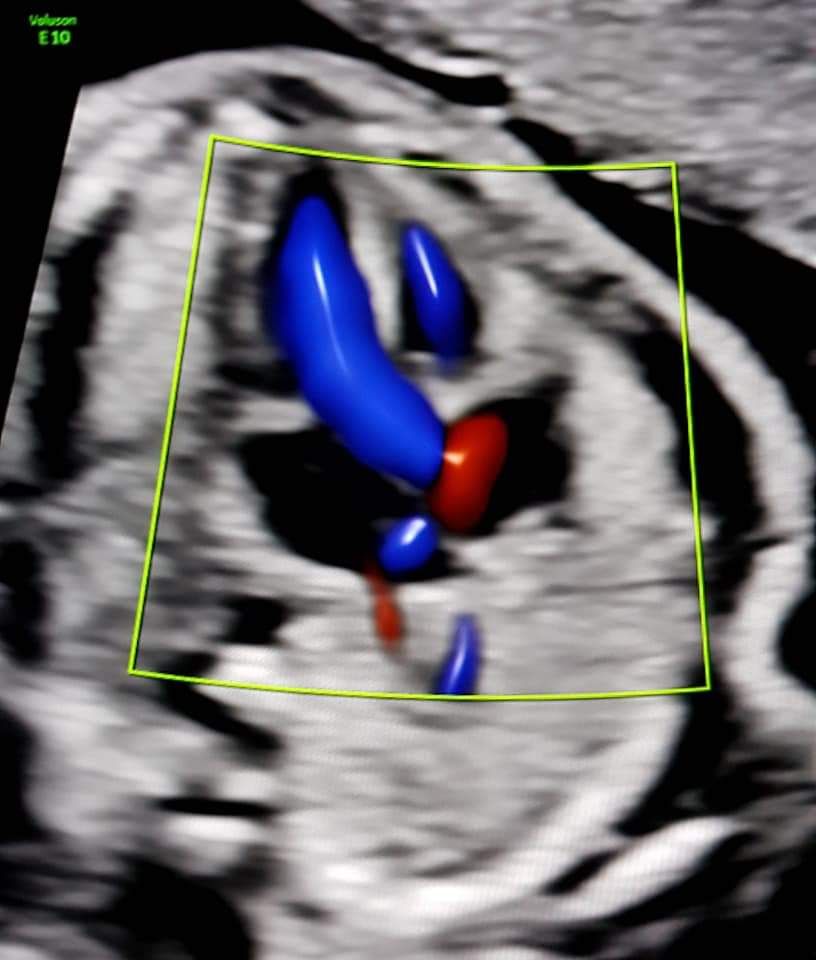

Foto e video

• Studio Ginecologico- Dott.ssa Nadia Fichera ecocardiografia fetale  •